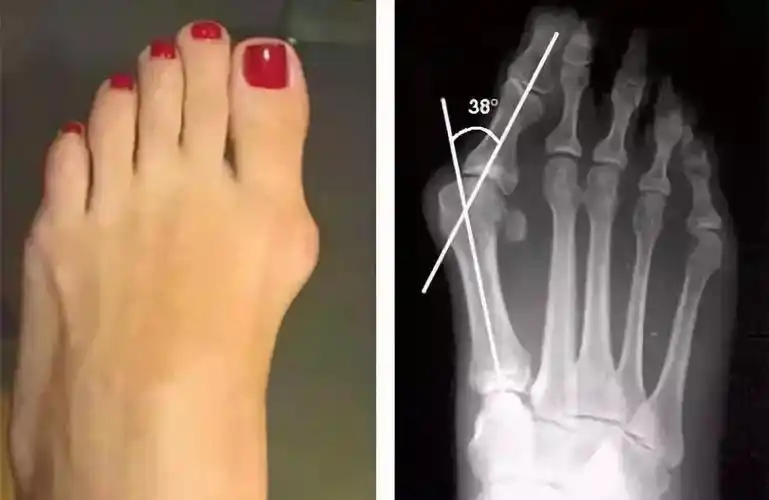

拇外翻?经常脚疼的人该注意了!